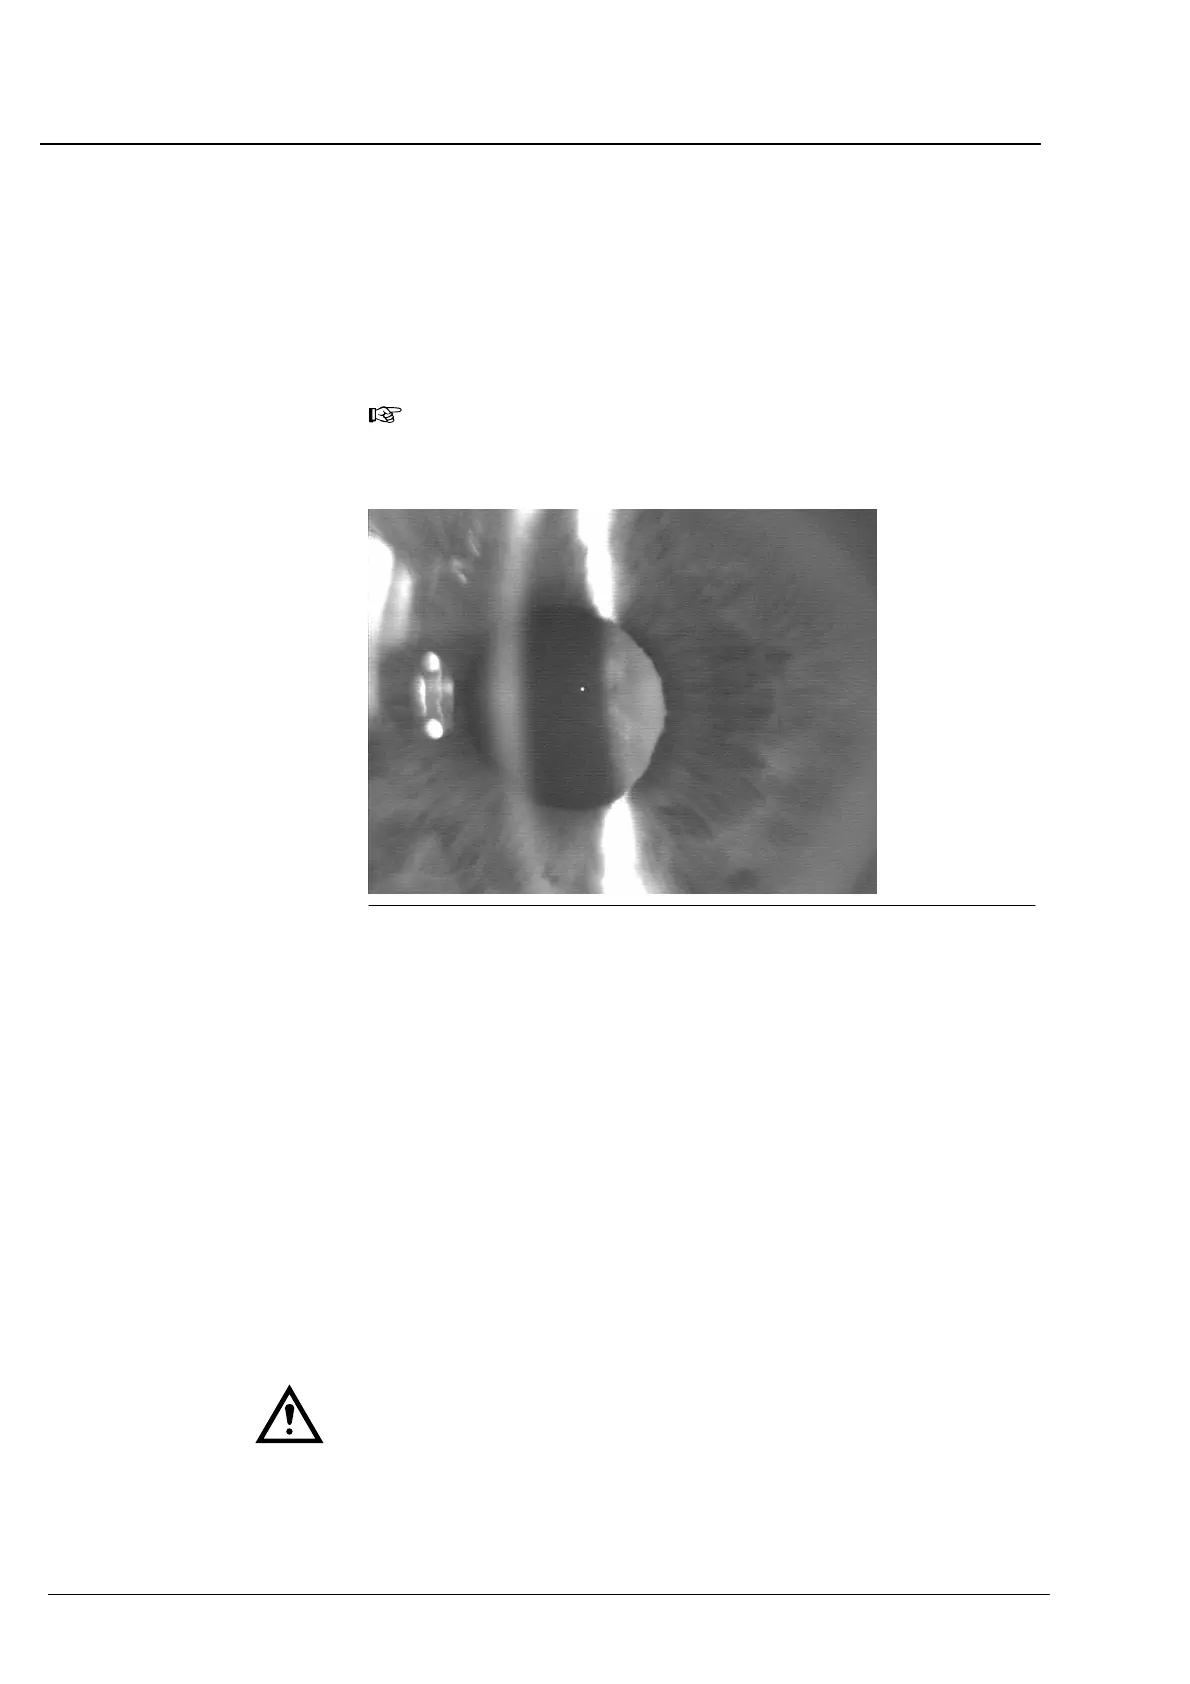

Fig. 63 Optimally adjusted optical section (lens with cataract)

Fig. 62 and Fig. 63 show optical sections of right eyes.

The patterns left of the corneal image are direct reflections of the

luminous light exit aperture of the lateral slit projector. These reflections

are not needed for the calculation of the anterior chamber depth. They

must not affect the image of the cornea (see below).

At the left margin of the picture, additionally reflections are visible

produced by the ambience (here, a window) being in front of the

patient. Depending on the lighting conditions in the examination room

it may also be possible that you see the front side of the IOLMaster

produced by the cornea. These artifacts do not disturb the measureĆ

ment of anterior chamber depth unless the significant image details

(images of cornea and crystalline lens) as well as the image of the

fixation point are significantly weaker than some kind of extraneous

light. This may be alleviated by slightly darkening the examination room.